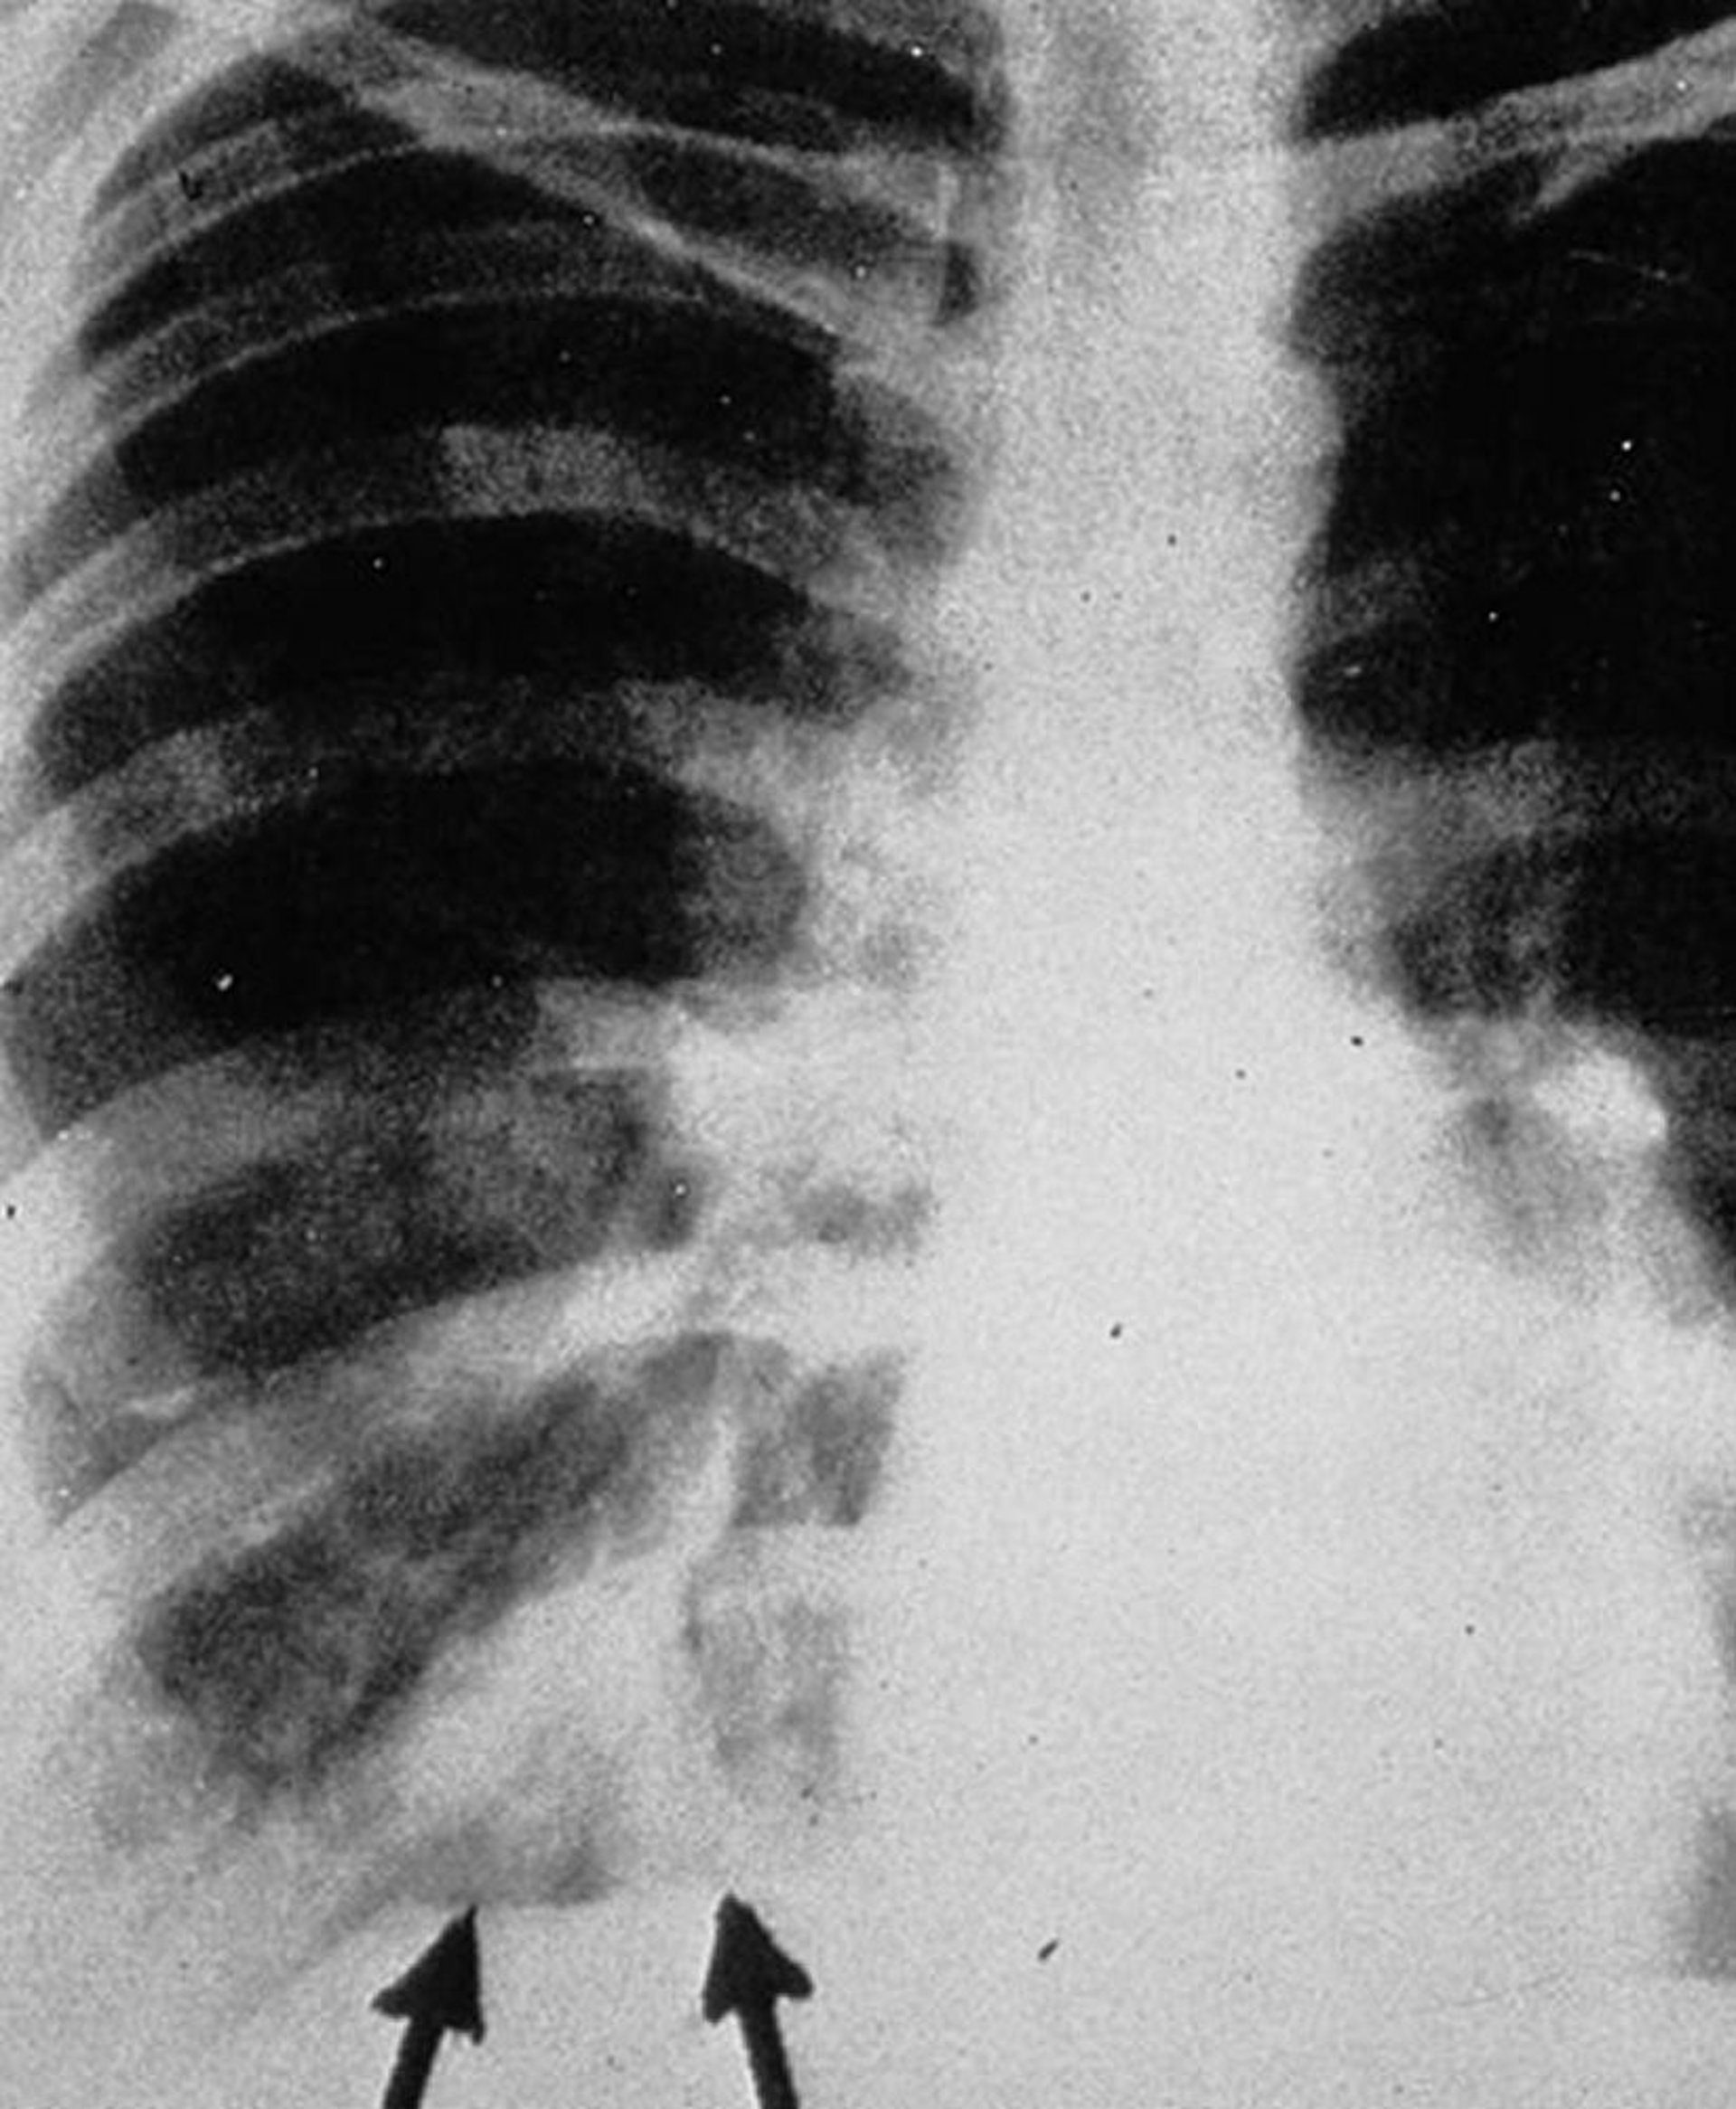

Das posteroanteriore Thoraxröntgenbild zeigt "behandschuhte Finger"-Schatten (Pfeile), die als verzweigte tubuläre Verdichtungen erscheinen und intrabronchiale Exsudate mit Bronchialwandverdickung darstellen.